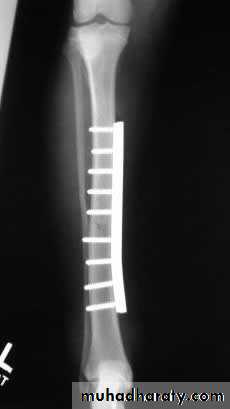

2-Plate fixation is best for metaphyseal fractures that are unsuitable for nailing. It is also sometimes usedfor unstable tibial shaft fractures in children.

Operative treatment